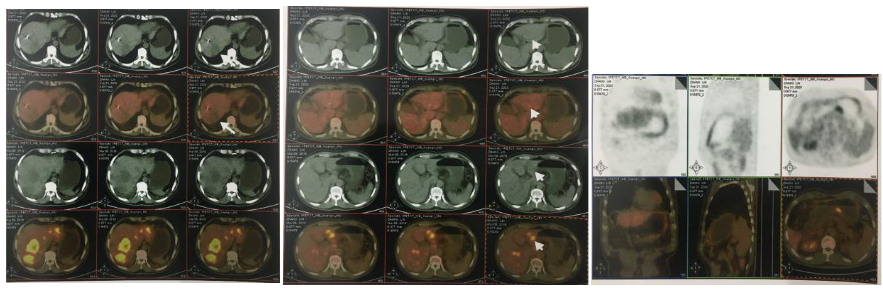

2018-03-08 PET/CT示:胃癌(?)并全身多发淋巴结转移、肝脏多发转移、双肺上叶多发转移;

2018-11-19 PET/CT

胃壁代谢稍增高但未见明确的肿物,肝内低代谢结节考虑转移瘤治疗后活性减低,纵膈及右肺门两个淋巴结代谢增高,考虑转移瘤活性尚存、左侧颞骨局部骨质破坏并代谢增高,考虑转移瘤。

胃癌并肝转移化疗后,肝内转移灶大致同期;

纵隔淋巴结转移瘤,复查大致同前。